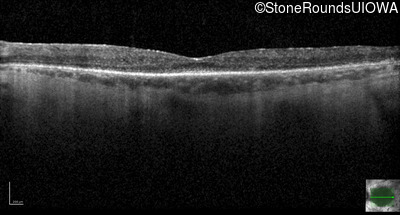

Optical Coherence Tomography - Left - 20/40 +1

Exemplar / OCT Stack